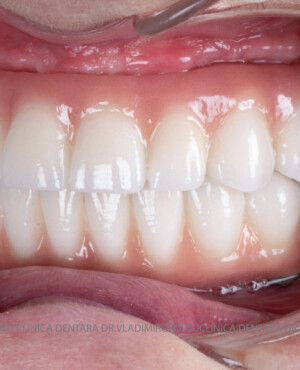

Caz 2

- Posibilitatea realizării unei proteze cu 12-14 dinți, oferind un aspect estetic natural și funcționalitate optimă.

- Proteză definitivă realizată din metaloceramică sau zirconiu, cu 12-14 unități (soluția recomandată).